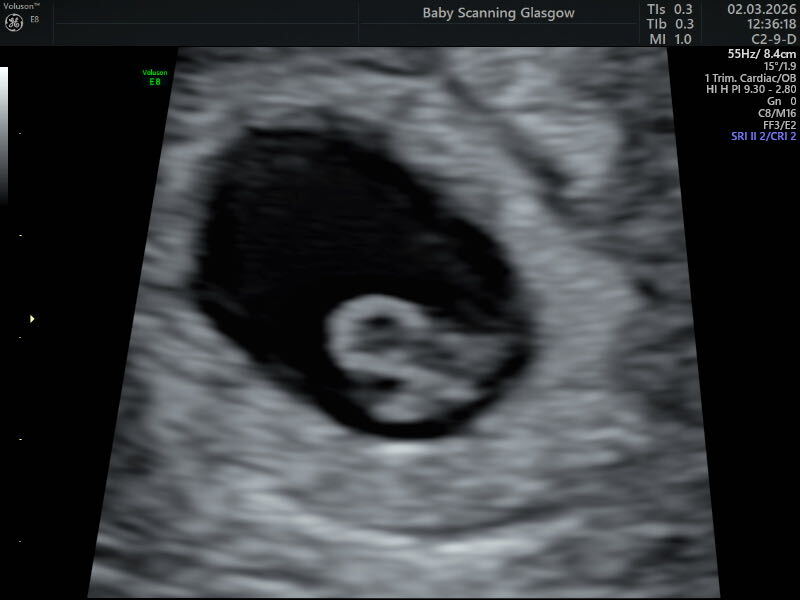

Testing 48 hours apart is all well and good but after losses it’s virtually impossible (for me anyway) to resist the twice a day urge. In any event, ‘twas indeed good progression and im now 9ish weeks 😊